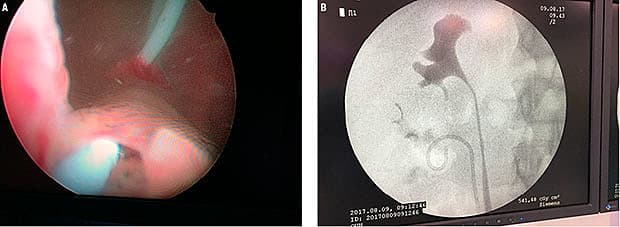

En 33-årig kvinde blev henvist til behandling for ektopisk ureter fra øvre anlæg af højre nyre. Hun havde haft inkontinens hele livet. Symptomerne var tolket som en stressinkontinens, og derfor blev der foretaget en tension-free vaginal tape-operation i 2010. Trods operationen var patienten fortsat inkontinent, hvilket førte til genhenvisning. Der blev foretaget bilateral retrograd pyelografi, CT-urografi og renografi. Undersøgelserne viste et højresidigt dobbeltanlæg (A), hvor ureter fra nedre anlæg havde indmunding i

blæren, mens ureter fra øvre anlæg havde indmunding i urethra ved blærehalsen. En renografi inklusive splitrenografi viste normale forhold. En cystoskopi viste, at ureter fra øvre anlæg havde udløb ved blærehalsen (B).